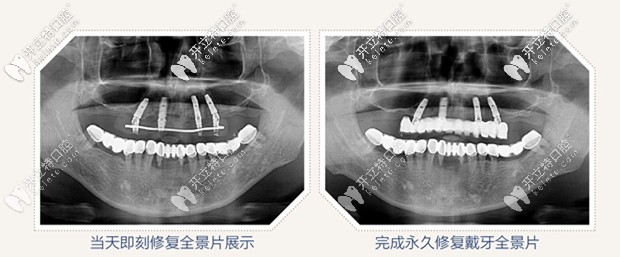

但是經(jīng)過拍片檢查,醫(yī)生說老爸的頜骨情況良好,可以進(jìn)行即刻種植,為了保證植體植入的準(zhǔn)確性,醫(yī)生給的治療方案是采用數(shù)字化導(dǎo)板微創(chuàng)精準(zhǔn)植入,同時較少了傳統(tǒng)翻瓣手術(shù)的痛苦。

all on 4即刻種植,只需要植入4顆種植體,就把老爸上半口牙就全給修復(fù)啦,并且是當(dāng)天修復(fù),當(dāng)天戴牙啊,感覺太神奇啦!

給老爸做的all on 4半口即刻種植牙花了10萬左右, 價格還是可以接受的,畢竟這做完種植牙的效果擺在這呢,上下半口牙齒恢復(fù)了咀嚼功能,近距離交談也看不出來做了種植牙,還有感覺老爸瞬間年輕了許多。